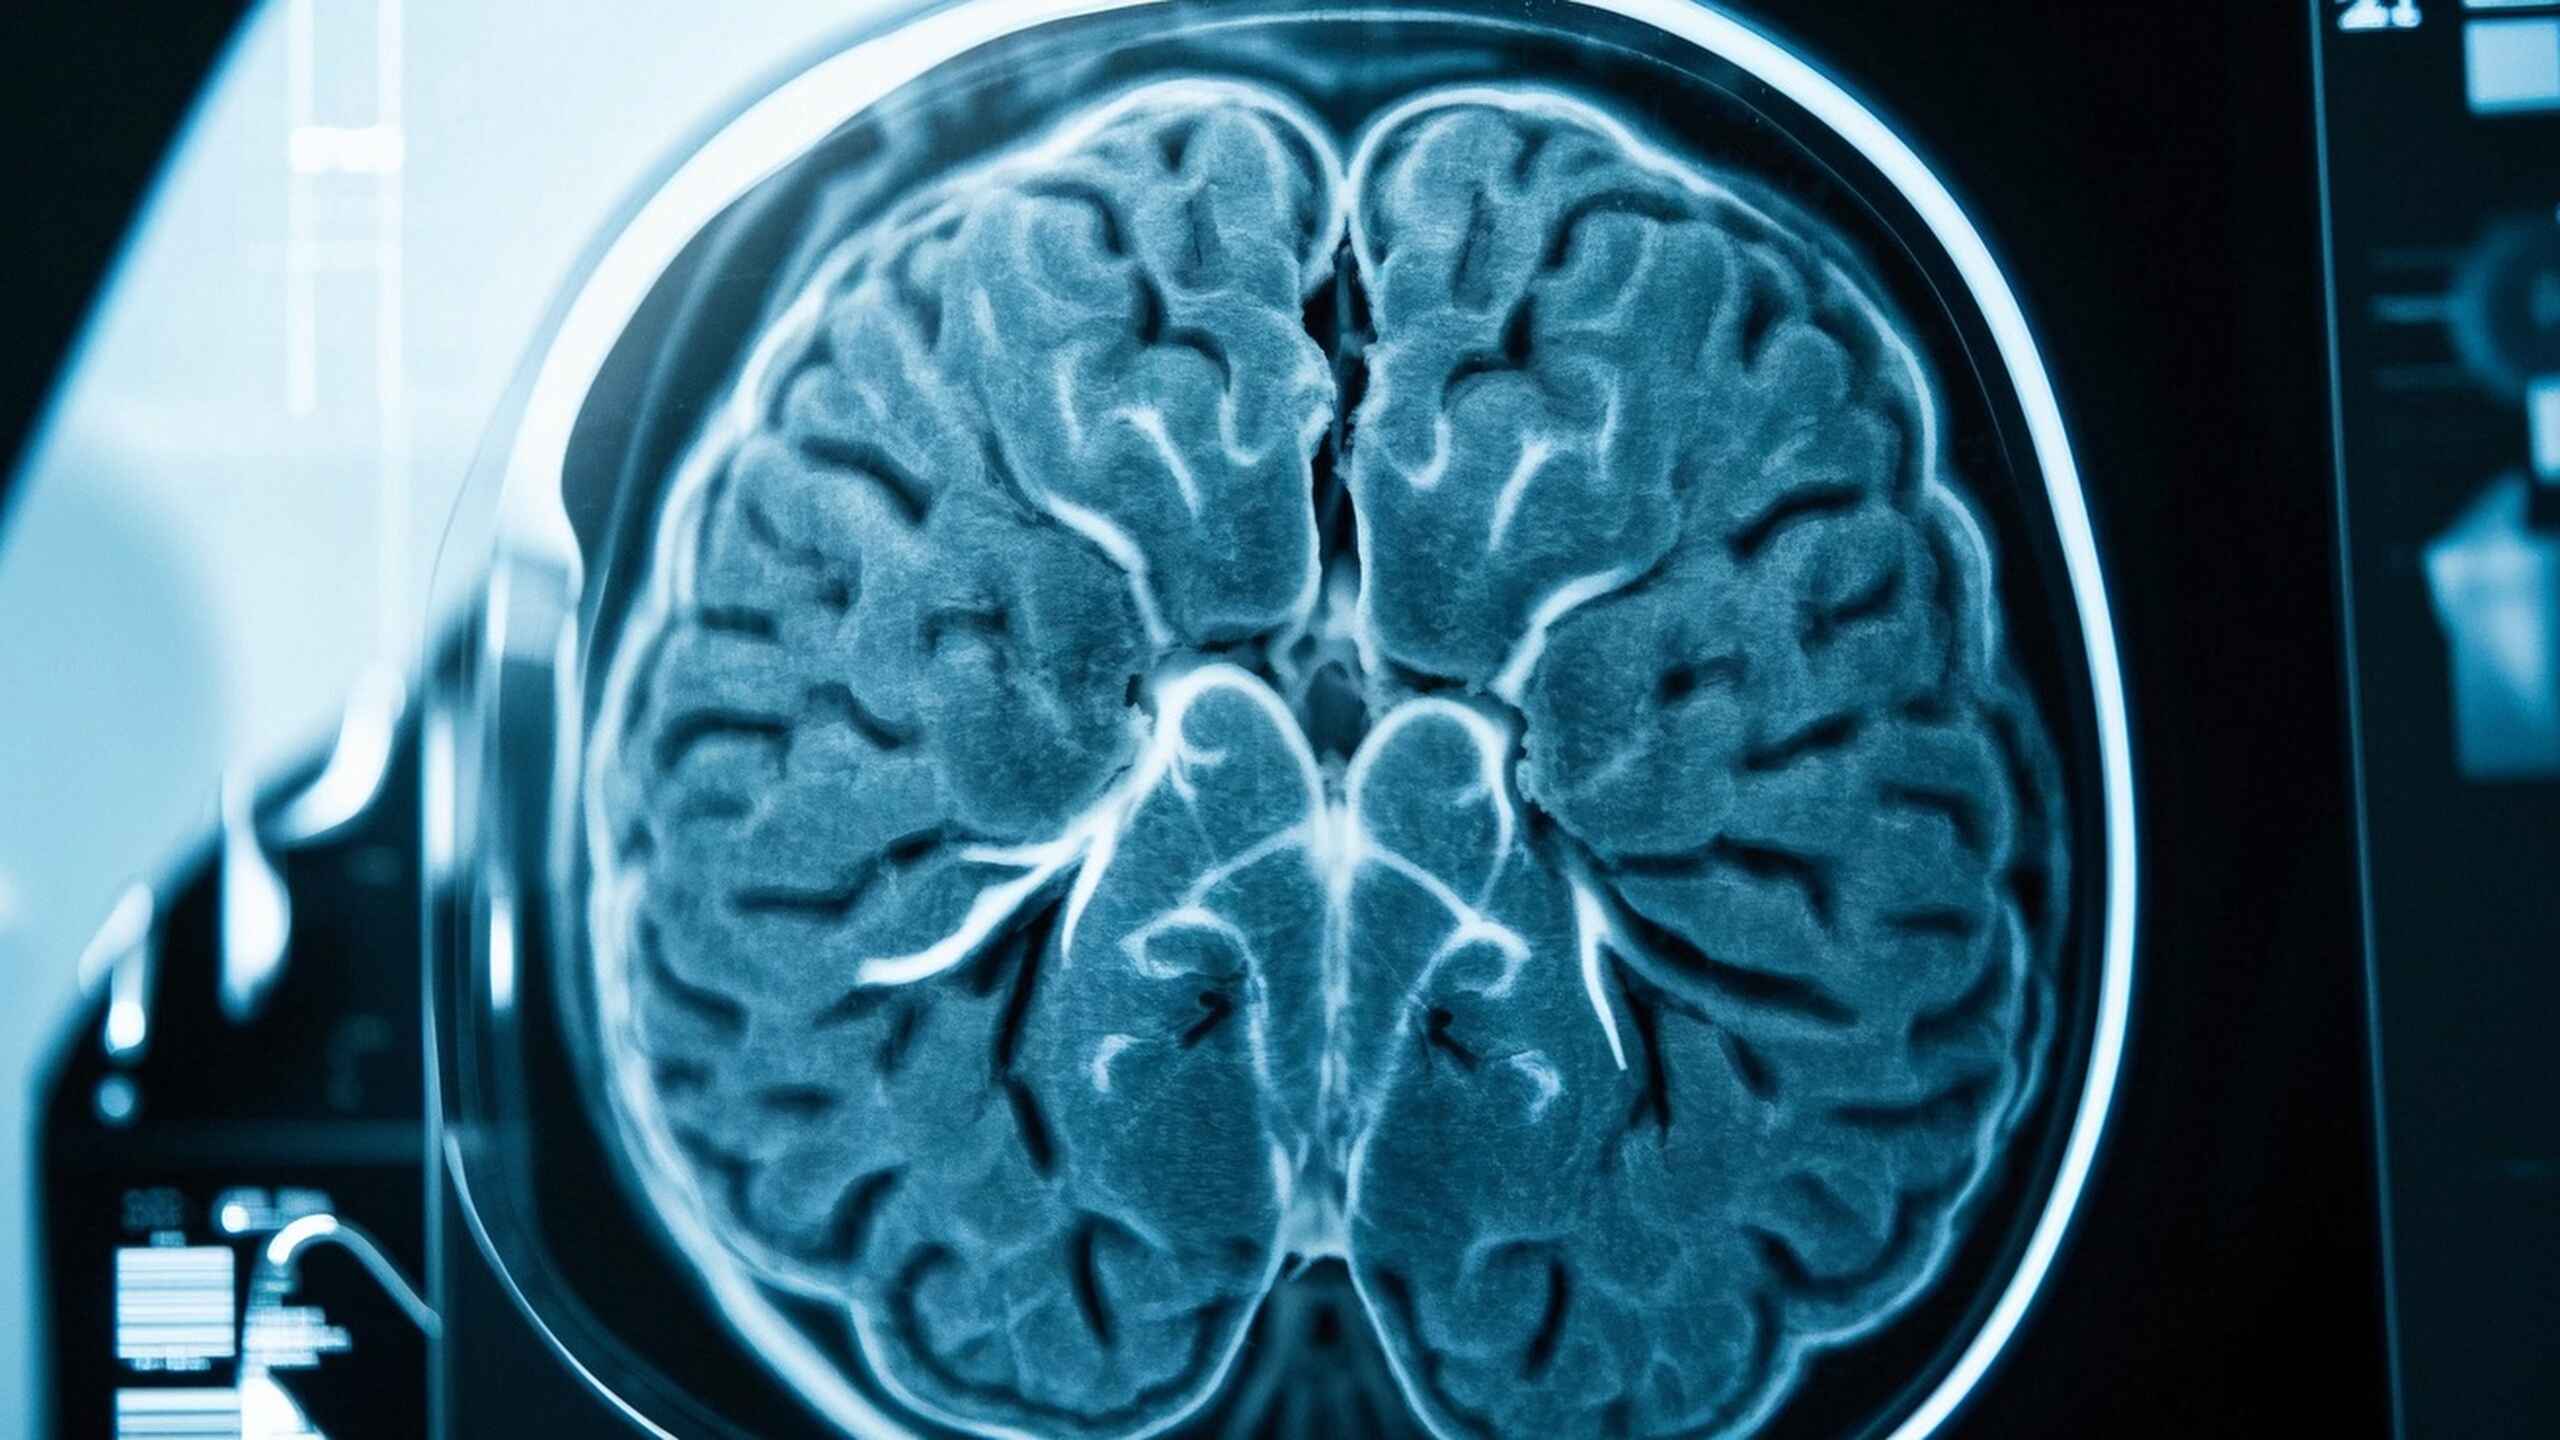

磁共振成像:普通MRI与增强MRI的全面对比与应用

本文深入探讨了磁共振成像(MRI)的基本原理,普通MRI与增强MRI的区别与适用场景,并提供患者在检查前的饮食建议和注意事项,帮助读者更好地理解MRI,提高健康管理意识。